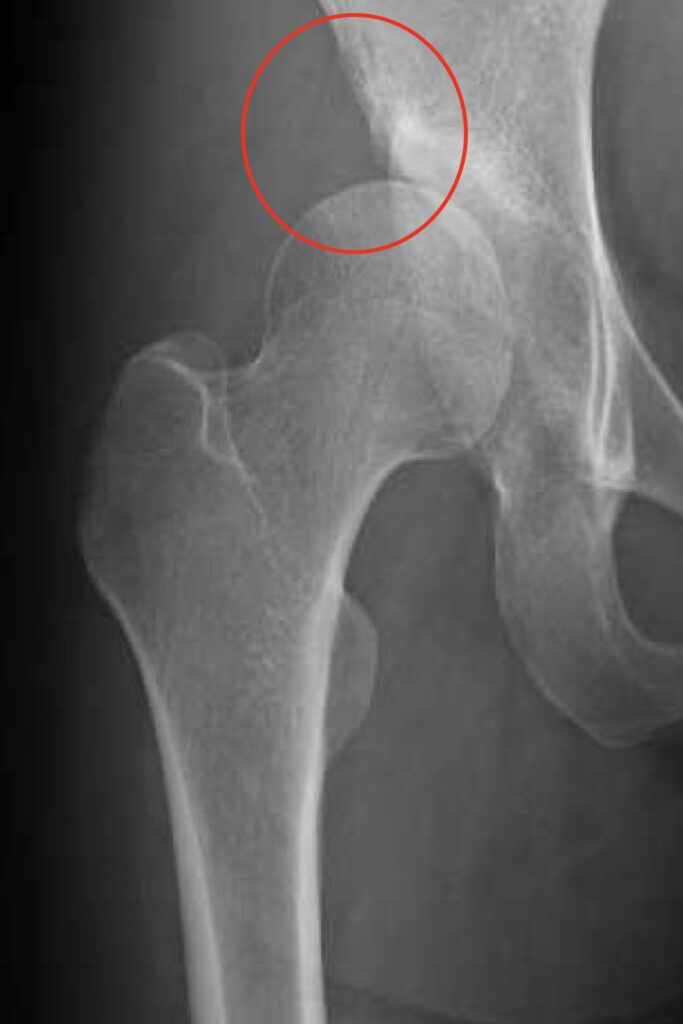

股関節の中心である大腿骨頭が壊死してつぶれるために痛みを生じる病気です。アルコールの多飲やステロイドの使用に関連しているとも言われていますが、いまだにはっきりしておらず国の難病に指定されています。骨頭の破壊が強ければ人工股関節置換術が必要になることがあります。

大腿骨頭壊死のレントゲン